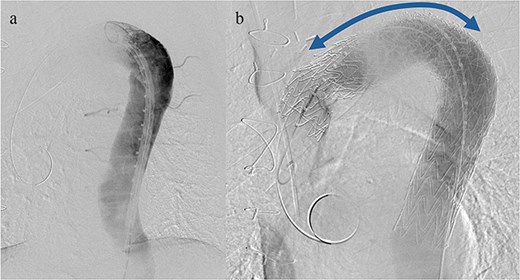

An 83-year-old man presented at our hospital with intermittent hemoptysis. Two years before, he had undergone total arch replacement with FET insertion using a 29 × 120 mm Frozenix J graft (Japan Lifeline, Tokyo, Japan) for a 55 mm aortic arch aneurysm. The Frozenix J graft is a commercially produced open stent graft with an internal skeleton made of nickel-titanium alloy. One year after surgery, postoperative contrast-enhanced computed tomography (CT) showed a reduction in the aneurysm diameter to 49 mm, with no endoleaks (Fig. 1a).

(a) Contrast-enhanced CT 1 year after total arch replacement with FET showing a reduction in aneurysm diameter from 55 mm to 49 mm, with no evidence of endoleak. (b) Contrast-enhanced CT 2 years after total arch replacement with a FET, showing an increase in aneurysm diameter to 56 mm.

CT revealed no endoleak, but the aneurysm had enlarged to a diameter of 56 mm (Fig. 1b). Three-dimensional CT revealed straightening and proximal migration of the FET (Fig. 2). No clear signs of pulmonary parenchymal hemorrhage or findings suggestive of the mass were reported. Laboratory tests indicated mild anemia, with a hemoglobin of 9.7 g/dL and hematocrit of 29.0%. No infectious or inflammatory diseases that could cause hemoptysis were identified.